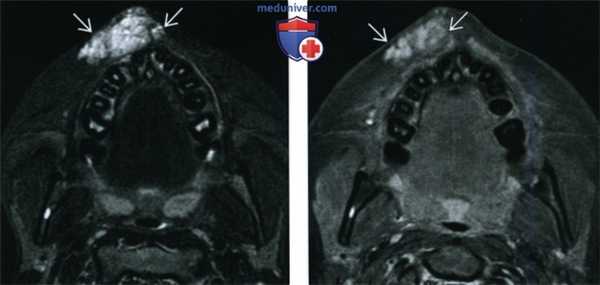

(Слева) При аксиальной МРТ Т1ВИ С+ FS в левой височной мышце визуализируется венозная мальформация, умеренно накапливающая контраст; в левой гемисфере мозжечка определяется врожденная венозная аномалия, в области моста мозга также визуализируется вероятная венозная аномалия меньшего размера или телеангиэктазия.

(Справа) При аксиальной МРТ Т1ВИ С+ FS в левой височной ямке визуализируется венозная мальформация, неравномерно накапливающая контраст.

(Слева) При аксиальной МРТ STIR в подкожных тканях в области верхней губы определяется венозная мальформация в виде объемного образования с бугристыми краями, хорошо отграниченного от окружающих тканей. Патологические изменения со стороны костей и зубов отсутствуют.

(Справа) При аксиальной МРТ Т1ВИ С+ FS y этого же пациента визуализируются патологически расширенные венозные сосуды, умеренно и неравномерно накапливающие контраст.